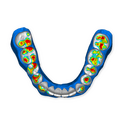

The DSD Interdisciplinary is a digital wax up of the upper and lower arches, designed considering a facially-driven, clinical and functional analysis of the patient.

It is our most comprehensive planning option, and includes all the 3D treatment simulations needed for each case, such as ortho, perio, implants, grafts and orthognathic surgery.